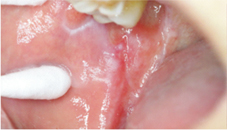

口腔扁平苔癬是一種慢性發炎性的口腔黏膜病變,為人體免疫失調而造成的局部自體免疫疾病,發病率約占總成年人口的百分之一到二;在性別比例上,女性多於男性,特別是中老年女性。在口腔內,口腔扁平苔癬好發於頰黏膜、舌頭、牙齦、嘴唇,且多為兩側性或多發性出現。在臨床上可以再區分為六種型態,分別是:網狀型(reticular type)、丘疹型(papular type)、斑狀型(plaque type)、萎縮/糜爛型(atrophic/erosive type)、潰瘍型(ulcerative type)以及水?型(bullous type),並且這六種型態並非只會單獨出現,常可能有其中的二到三種同時發生於口腔中。網狀型,顧名思義會看到白色網狀的條紋交錯排列(如:圖一);丘疹型則會出現小顆粒的突起;斑狀型則呈現白色的斑塊(如:圖二),此三種型態可歸為非糜爛型的口腔扁平苔癬,除了外觀上的變化外,往往沒有明顯的臨床症狀;糜爛型的口腔扁平苔癬則會在黏膜上看到一些紅色的斑塊,且周圍伴隨有白色的放射線狀條紋(如:圖三),而水?型相對於其他幾種型態,則較為少見。其中,糜爛型和潰瘍型的口腔扁平苔癬,常伴隨有疼痛或是較為敏感等口腔黏膜不適的症狀,這些不適的症狀往往是患者前往就診的原因。另外,有些患者的口腔牙齦也會有發炎紅腫的現象,稱為「脫屑性牙齦炎」(desquamative gingivitis)。

圖三、糜爛型口腔扁平苔癬位於頰黏膜